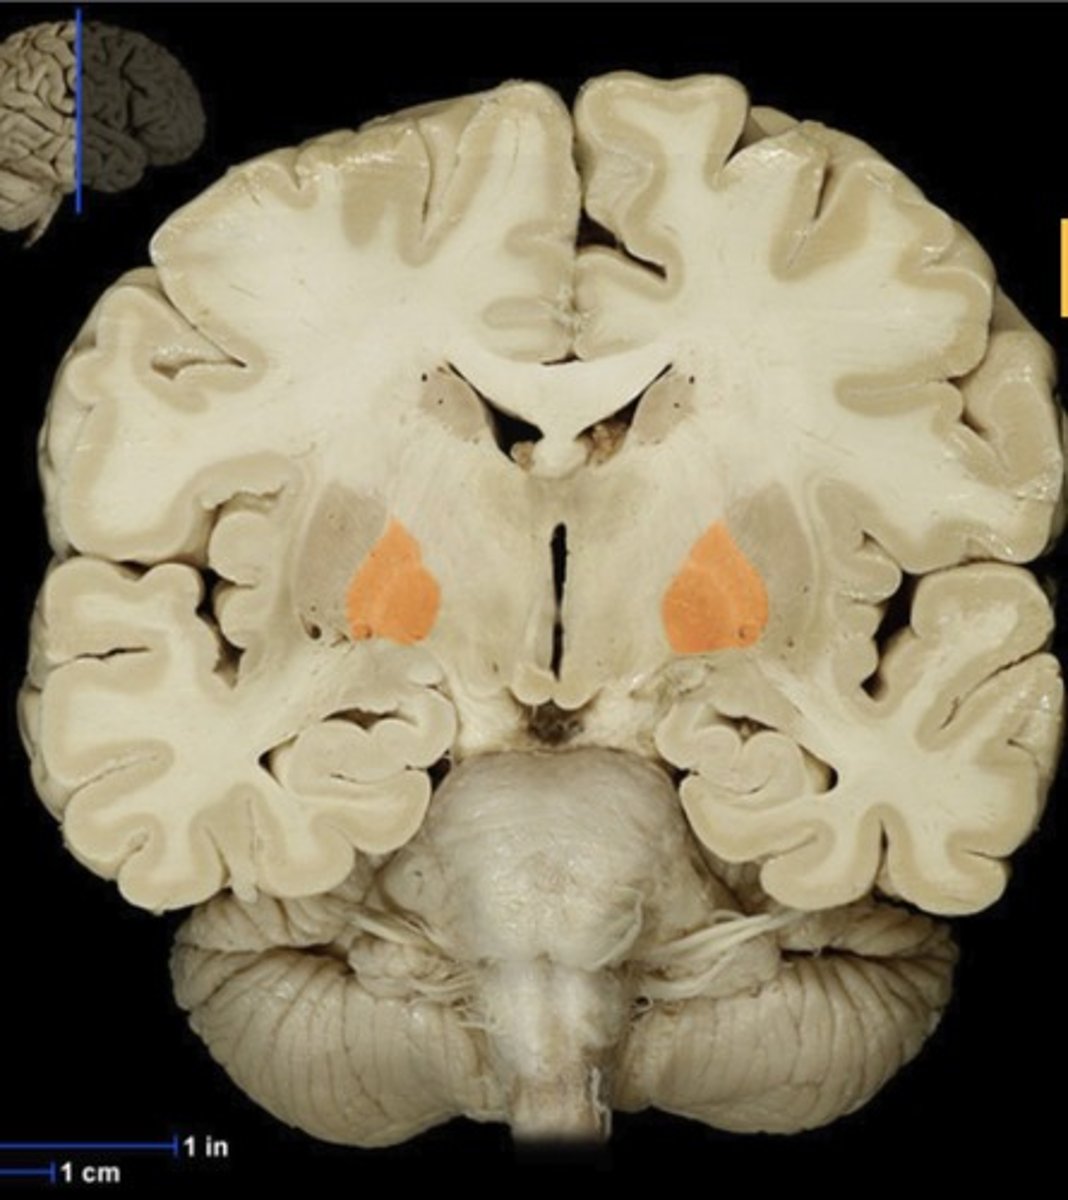

Name this structure

Gray matter (anterior view of coronal section)

Name this structure

White matter (anterior view of coronal section)

Name this structure

Name this structure

Name this structure